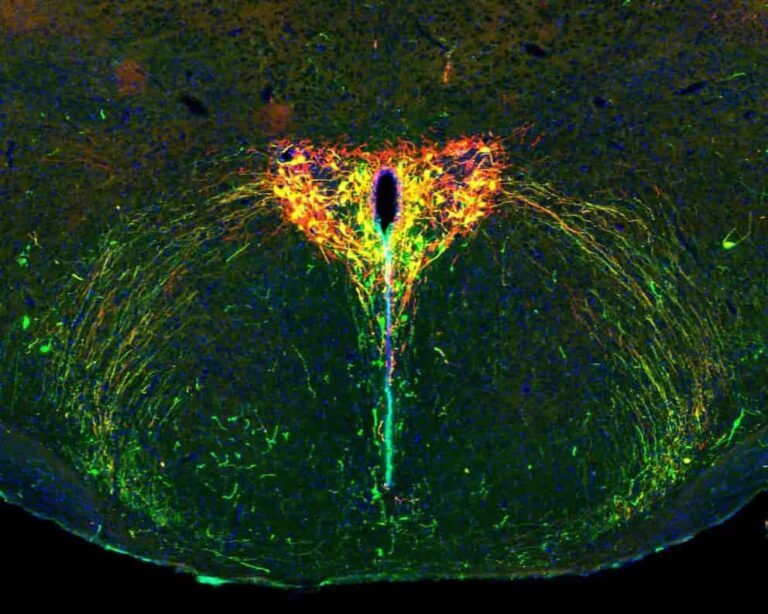

InvestigaciónVacunas e IAEnsayos, vigilancia genómica y salud digital avanzan como herramientas estratégicas.